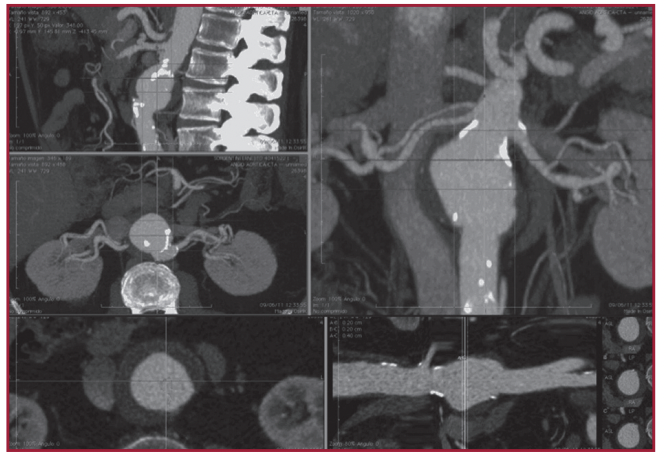

Los pacientes con aneurismas toracoabdominales tipo IV se caracterizan anatómicamente por la presencia de una dilatación aórtica visceral que determina la falta de un cuello proximal aórtico adecuado para el anclaje de las endoprótesis convencionales. Para tal fin existen injertos especialmente diseñados con fenestraciones. En esta comunicación se describe la experiencia de un grupo quirúrgico en la utilización de endoprótesis fenestradas. Fueron tratados seis pacientes. Todas las endoprótesis fueron implantadas con éxito, respetando 20 vasos viscerales. Este abordaje constituye hoy una alternativa válida para el tratamiento de este grupo de pacientes candidatos a cirugía convencional de alto riesgo.